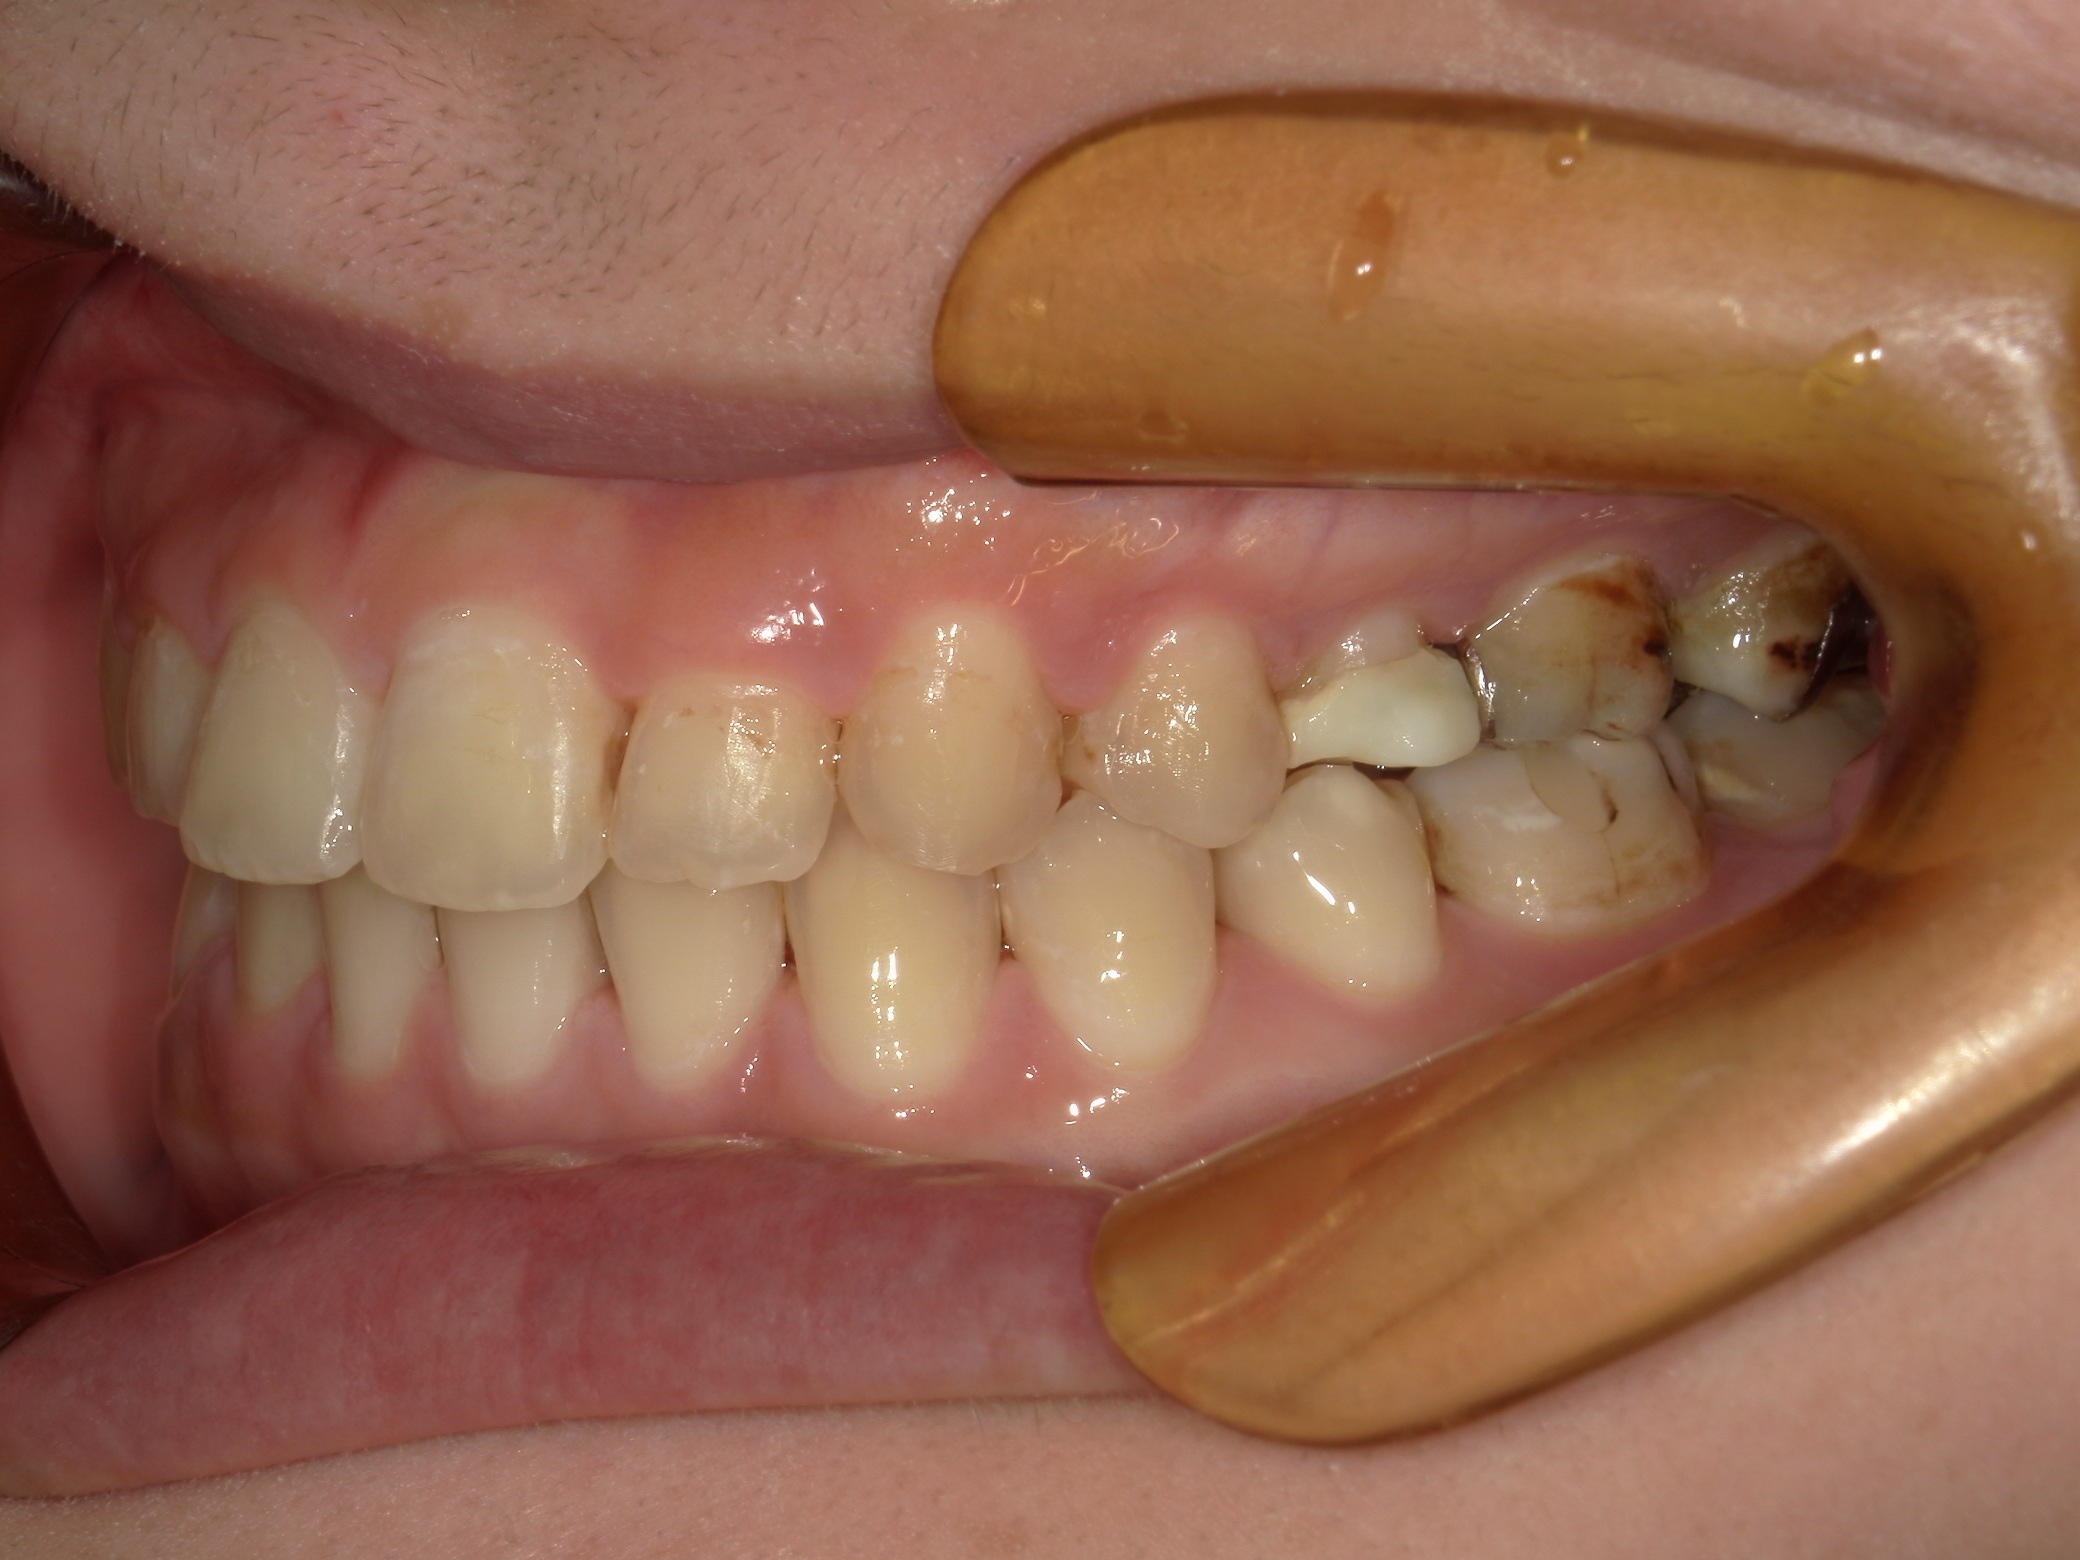

口内右

治療前

治療後